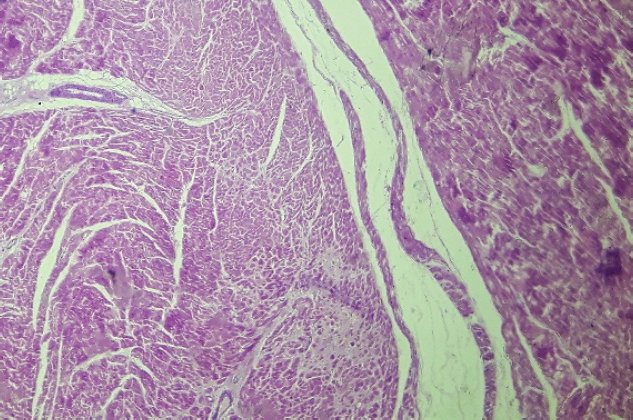

After 24 Holter monitoring, the patient died suddenly during physical activity. Permission for conducting necropsy was obtained from the animal owners. Postmortem examination showed marked cardiomegaly (heart weight bigger than 13 g/kg body weight). No lung edema, pleural effusion or ascites were observed. The heart was explanted and preserved in 10% formalin and then sent for examination to the pathology service of the Hospital Santojani (Buenos Aires), where fragments from both ventricles and the septum were processed with the routine technique to make paraffin-embedded blocks. 4 μm thick sections were cut and stained with hematoxylin-eosin (H&E). Adipose and fibroadipose replacement of the right ventricle free wall of up to 50% of its thickness was observed. These lesions had a predominantly subepicardial distribution. Subepicardial fibroadipose replacement of the left ventricle with involvement of the septum was also observed (Fig. 3). In addition, adipose tissue was also observed in the left ventricle, affecting the base of implantation of the papillary muscles at the septum (Fig. 4). In areas of the left ventricle, co-existence of perivascular fibrosis, myocardial fibrosis suggestive of previous necrosis, and interstitial fibrosis were detected (Fig. 5). In addition, wavy fibers in the myocardium in both ventricles were observed. Clusters of myocardial fibers were also observed within all areas of adipose tissue deposition.

Fig. 5. Free wall of the left ventricle (H&E, 100×). Histopathological image showing connective tissue and adipose tissue deposition, with perivascular fibrosis and interstitial fibrosis.